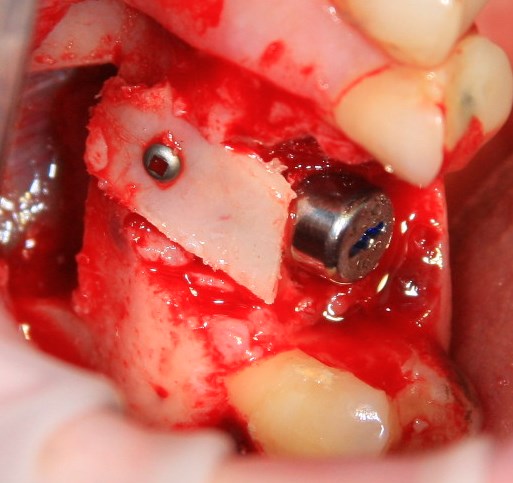

Немедленная имплантация — оптимальное решение в любой клинической ситуации